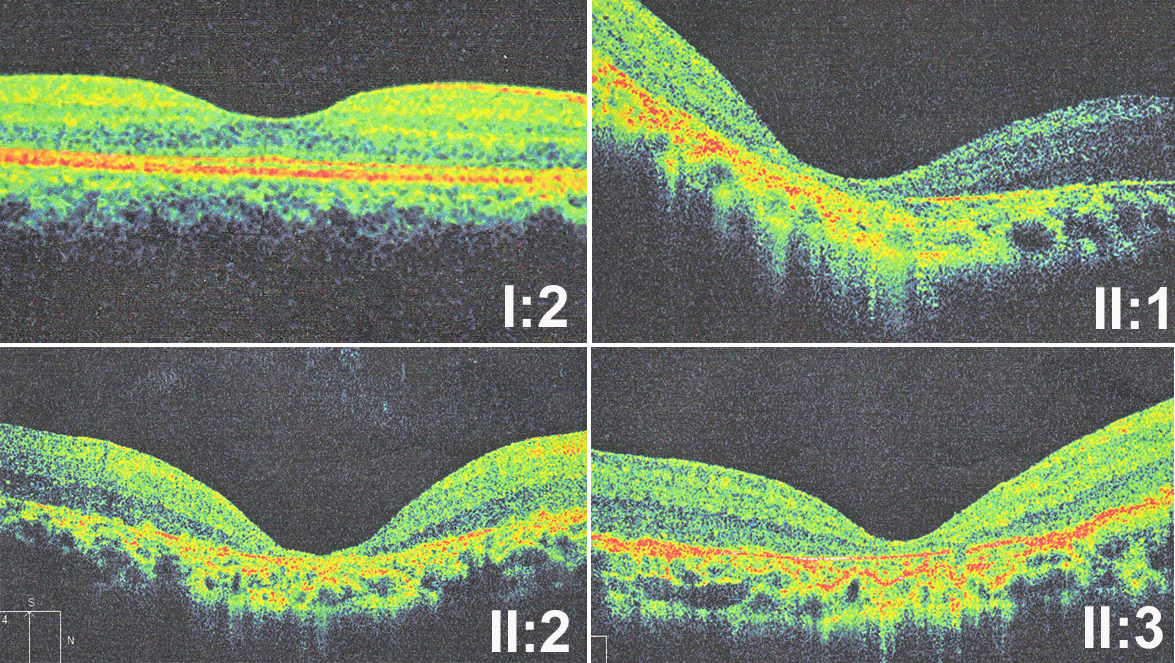

Figure 5. Optical coherence tomography of three patients shows thinning of the retina and loss of photoreceptor layers compared with

the mother (I:2) who has normal fundus. Patient II:1 had similar changes, compared to patients II:2 and II:3. It indicated

the affected member II:1 who carried a third mutant allele in a second gene may not have more severe phenotypes than other

affected members in the family.